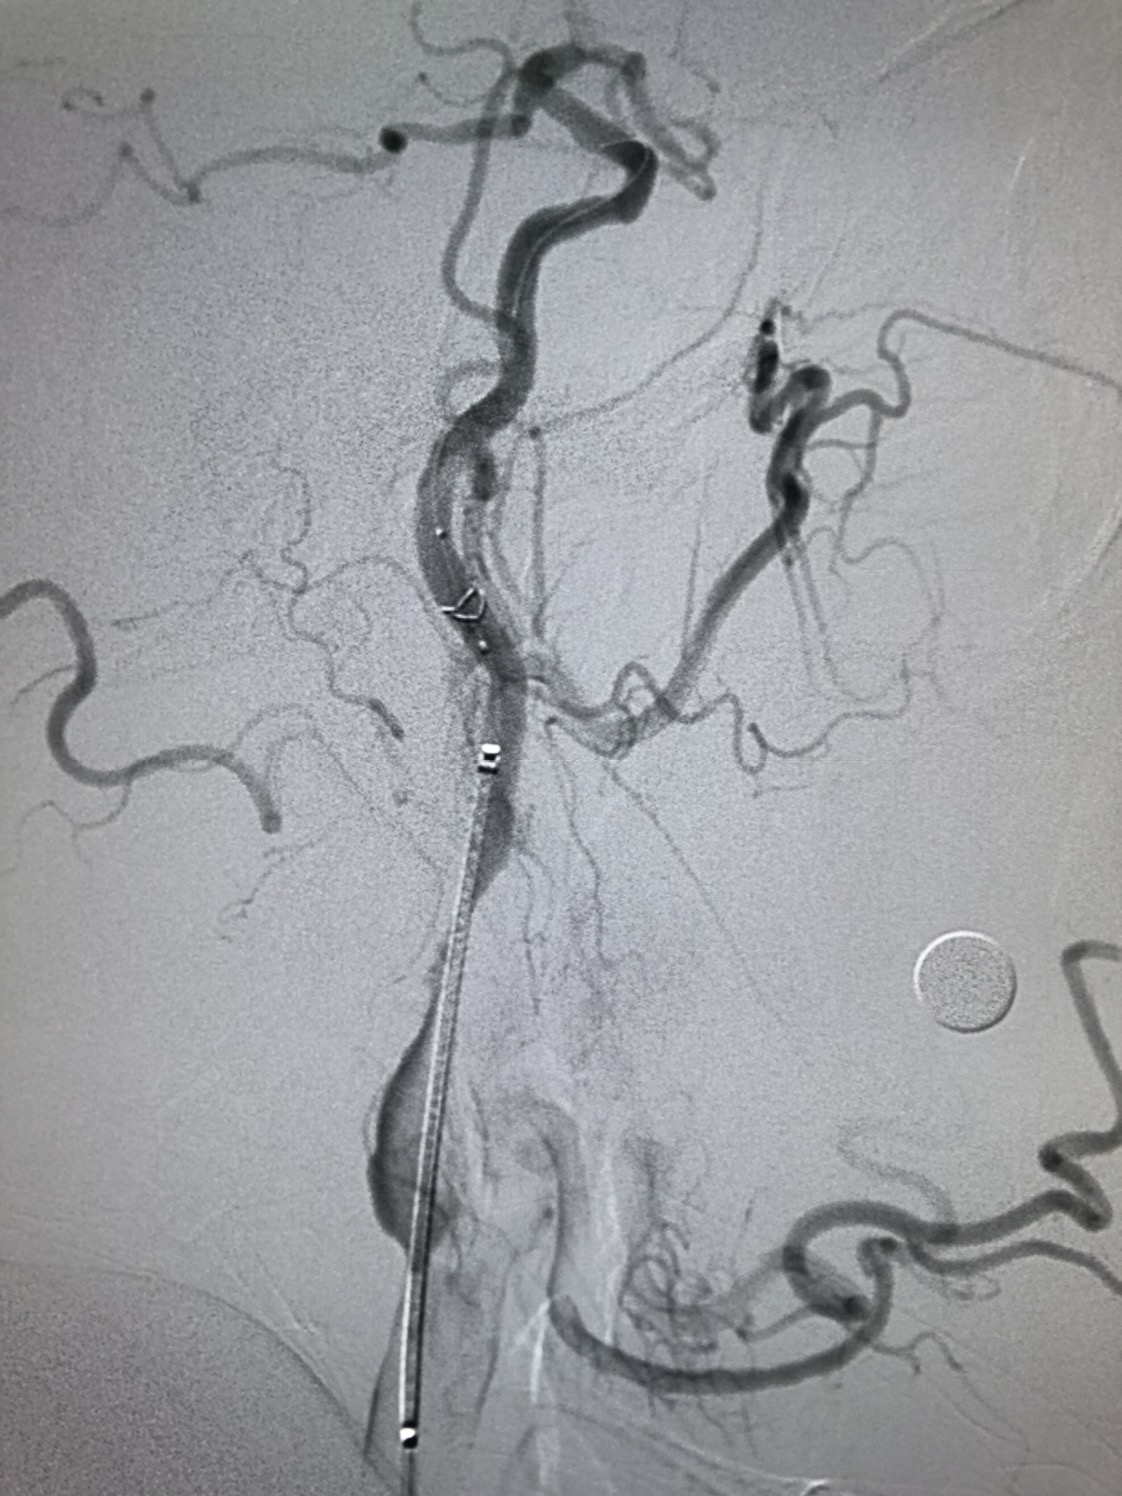

远端保护伞保护下,4/30球囊预扩后狭窄改善

WALLSTENT 9/40支架定位准确后释放

支架释放后狭窄解除

支架完全覆盖斑块,狭窄解除,支架形态柔顺贴合血管,无明显残余狭窄